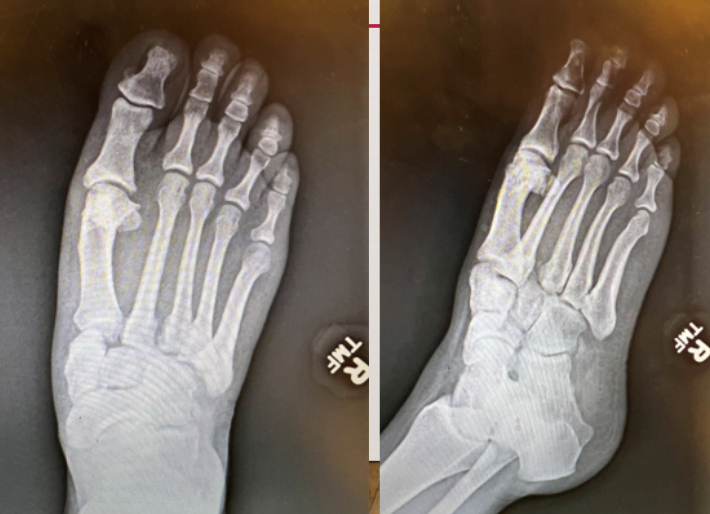

- Radiology: Lisfranc Injuries

- MOI:a xial load on plantar flexed foot or severe twisting action

- Disruption of Lisfranc ligament- consisting of dorsal ligament, interosseus ligament and plantar ligament-🡪 disruption of midfoot

- What to look for on exam?

- Pain and swelling in midfoot

- Ecchymosis to plantar surface ( PATHOGNOMONIC)

- Weight bearing xrays are super helpful